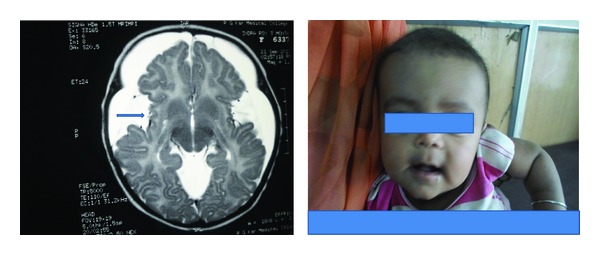

A one-and-half-year-old Muslim male child born of consanguineous marriage presented with gross developmental delay and large head size, with the child having history of recurrent episodes of seizures. Although he could smile responsively and feed well, complete head control had not been achieved. On examination he had macrocephaly (OFC 52 cms, expected 47 cms), broad nasal root, hypertelorism, thin sparse hypopigmented hair, and gross developmental delay. Investigations including peripheral blood picture, serum electrolytes, blood glucose, serum ammonia, and liver function test were normal. Urine for tandem mass spectrometry (TMS) report was suggestive of glutaric aciduria. MRI (on T2 weighted MR) brain reveals frontotemporal atrophy, dilated sylvian fissures with open opercula (bat-wing appearance) with hyperintense lesions in bilateral basal ganglia, and the both frontal white matter and bilateral periventricular area suggestive of glutaric aciduria type 1 (Figure 1). Then the child was put on protein restricted diet with carnitine and riboflavin supplementation and anticonvulsant for seizure control. After 6 months of treatment anticonvulsant was withdrawn. After 1 year of followup he remained seizure-free and now he can sit without support, stand with support, and speak disyllable words and head size remained static.

Figure 1.

Showing patient with macrocephaly, typical facies, and MRI of his brain reveals frontotemporal atrophy, dilated sylvian fissures with open opercula (arrow), diffuse hyperintense lesions in bilateral basal ganglia, and both frontal white matter and bilateral periventricular area. Widening of the sylvian fissure gives the characteristic “bat-wing” appearance.